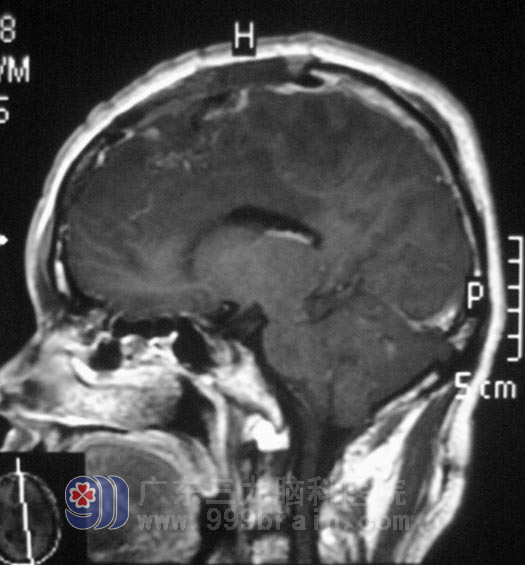

在广东三九脑科医院综合神经外科完善相关检查后,由鲁明主任主刀,在全麻下行“左额镰窦旁肿瘤切除术+去骨瓣减压术”,术中板障出血凶猛,显微镜下见灰白色肿瘤组织,肿瘤表面血管丰富,畸形明显,杂乱生长,肿瘤与大脑镰粘连紧密,并侵犯上矢状窦,脑组织肿胀明显,予行去骨瓣减压。手术顺利结束。术后头颅MR复查未见明显肿瘤残留。

王先生手术效果良好,已康复出院。术后病理结果为:脑膜瘤(上皮型,WHO I级)。